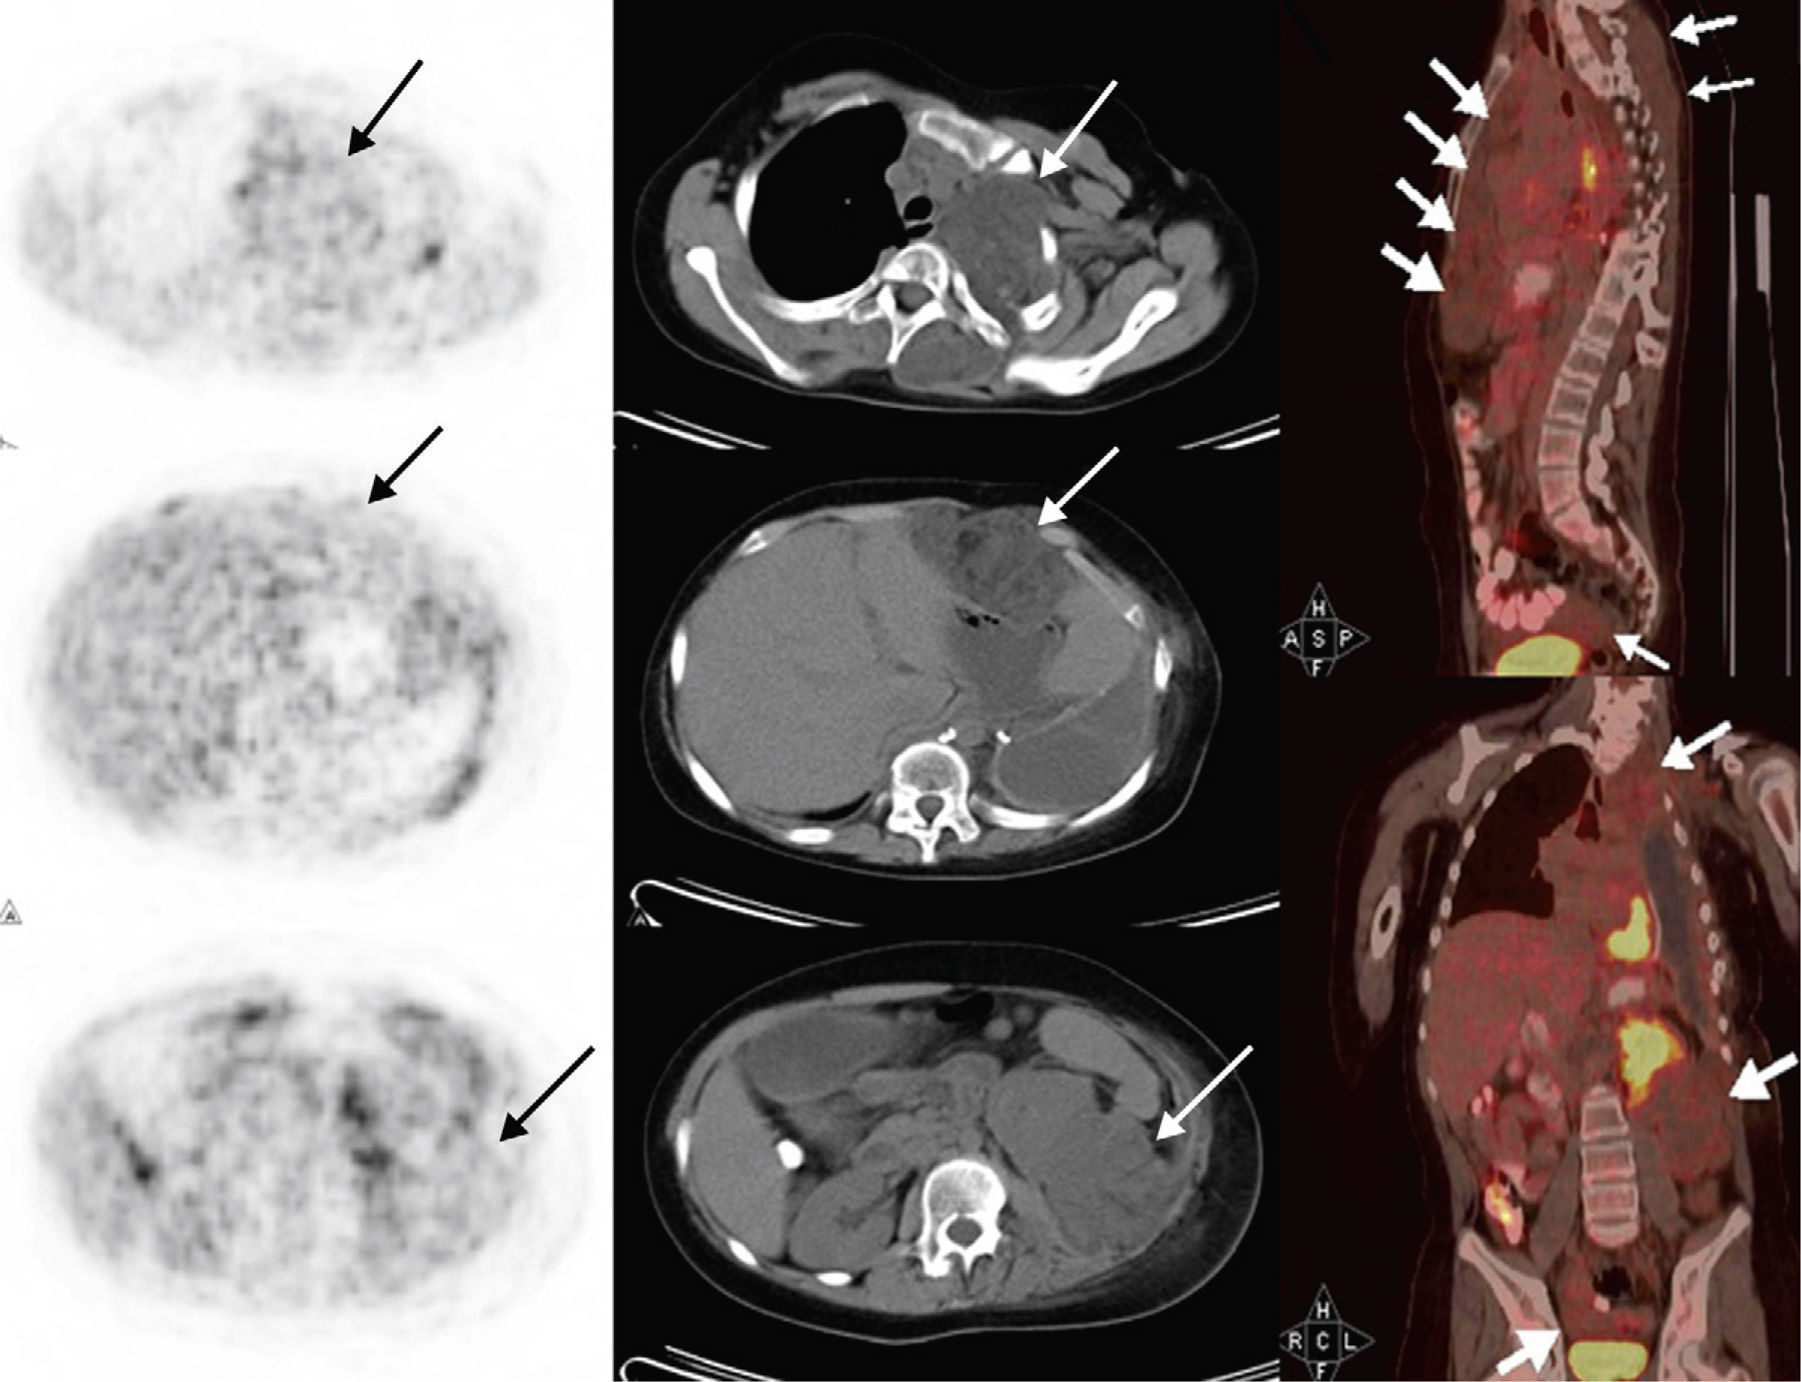

The role of FDG PET/CT in management of soft tissue and bone sarcomas has been described in many studies up-to-date. However, contribution of PET/CT to diagnosis and treatment in some types of sarcomas that are seen with low incidence has not been identified properly yet. Clear cell sarcoma, synovial sarcoma of chest and myxoid lyposarcoma are rare types of sarcomas. We aimed to describe the FDG uptake patterns of these rare tumors and find out the role of FDG PET/CT in management of disease.